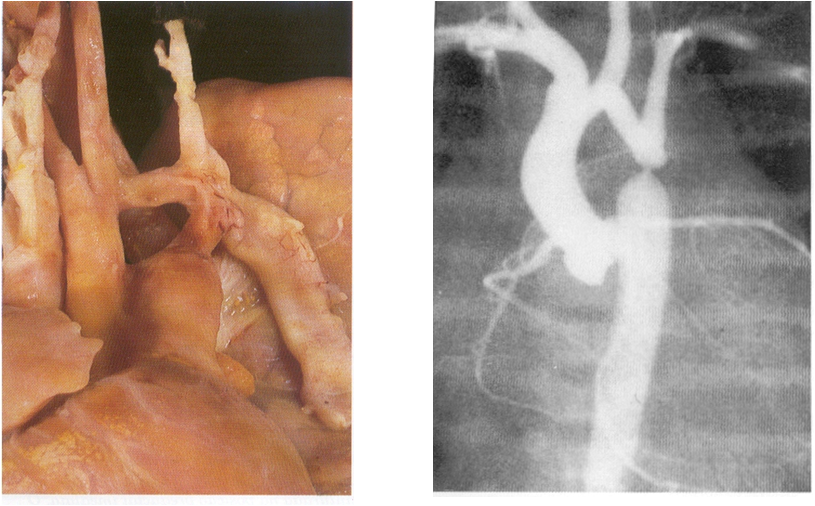

Tetralogia de Fallot

As 4 características da Tetralogia de Fallot são:

1- Estenose pulmonar.

2- Comunicação interventricular (CIV).

3- Cavalgamento da aorta sobre a CIV.

4- Hipertrofia do ventrículo direito.